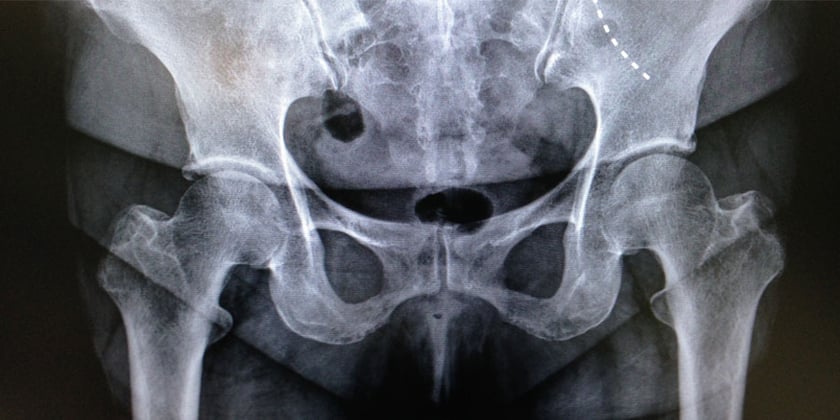

Die erste Anlaufstelle bei Beschwerden aller Art ist meist der Hausarzt, der bereits erste Abklärungen vornimmt. Wenn aber Schmerzmittel oder eine entsprechende Physiotherapie keine befriedigende Wirkung erzielen, sind die Fachärzte der Hüftorthopädie am Spital Emmental gefragt. Ronald Wanner: «Nebst einem ausführlichen Gespräch versuchen wir, den Beschwerden mittels radiologischer Basisdiagnostik auf die Spur zu kommen.» Dazu gehört das Röntgen und, falls nötig, ein MRI der Hüfte sowie weitere Untersuchungen. «Um eine präzise Diagnose zu stellen, braucht es oft viel Erfahrung. Wir behandeln in erster Linie Patienten und nicht deren Röntgenbilder.» Denn es kommt nicht selten vor, dass die Schmerzursache woanders liegt, selbst wenn der Patient, die Patientin tatsächlich eine Hüftarthrose hat.